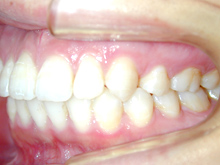

常滑市小林町在住 S.T様(15歳女性)

S.T様は下顎前歯の叢生が主訴でお母様と無料矯正相談で来院されました。

口を閉じる際に口元の緊張があり、横顔に突出感がありました。

以前に上顎前歯の部分矯正をされたご経験があるとお話しされておりました。

そのためか上顎犬歯の横幅(幅径)が通常より少なく思いました。

試料採取より診断の結果、上顎の前歯にも軽度の叢生があり、口元の緊張を改善し、

前歯の叢生の治療のために抜歯が必要であることを説明し、了承が得られたので本格矯正で治療をすすめることとなりました。

上顎前歯に軽度の叢生、下顎前歯に叢生がみられます前歯の上下の接触状態が緊密でなく軽度の舌癖の存在を疑います。

臼歯部は1歯 対 2歯で咬んでいます。